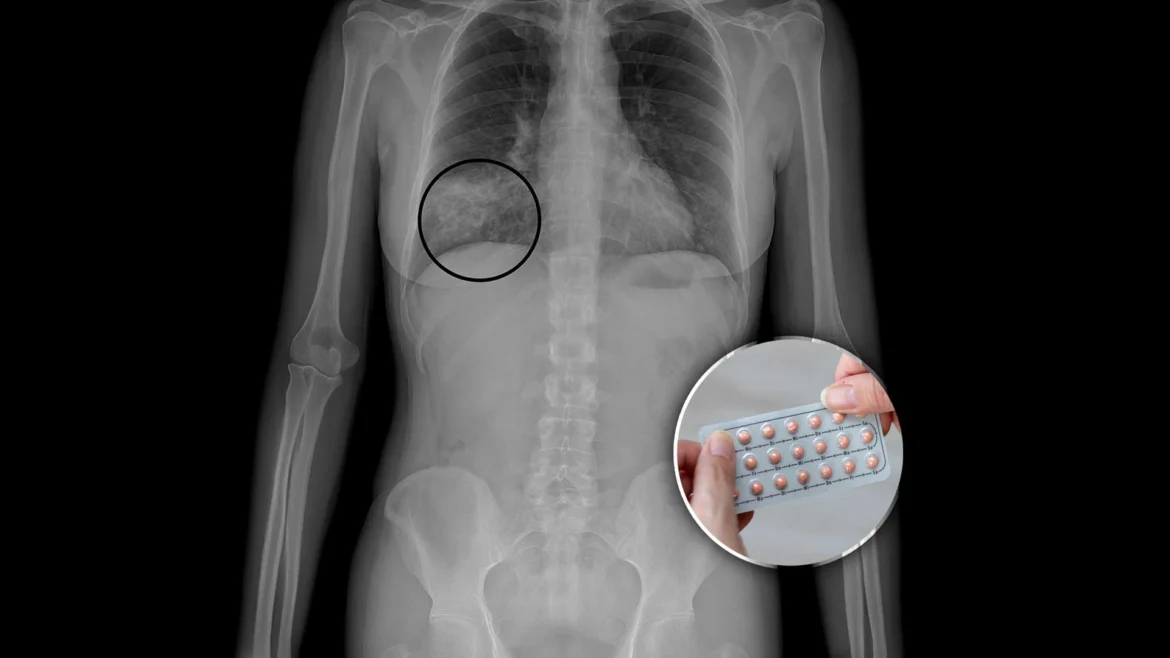

1. Sí aumenta el riesgo de algunos cánceres… pero protege contra otros

La OMS clasifica a los anticonceptivos hormonales combinados como carcinógeno tipo 1.

Esto no significa que causen cáncer automáticamente, sino que existe evidencia científica de que modifican ciertos riesgos.

📌 Aumenta ligeramente el riesgo de:

Cáncer de mama

Cáncer de cuello uterino

📌 Disminuye el riesgo de:

Cáncer de ovario

Cáncer de endometrio

Cáncer de colon

👉 La realidad es esta: el riesgo absoluto es bajo, pero existe, y toda mujer tiene derecho a saberlo antes de usarla.